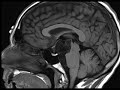

Epidermoid

These images demonstrate a lobulated T2 hyperintense, T1 hypointense, T2 FLAIR hyperintense, non-enhancing mass centered in the suprasellar and interpeduncular cisterns. The mass demonstrates restricted diffusion and is compatible with an epidermoid cyst. Most epidermoids are intradural and commonly involve the basilar cisterns as seen here. They tend to follow the signal of CSF, but do not completely suppress on FLAIR. Diffusion restriction is the defining imaging feature. Treatment is with surgical resection.